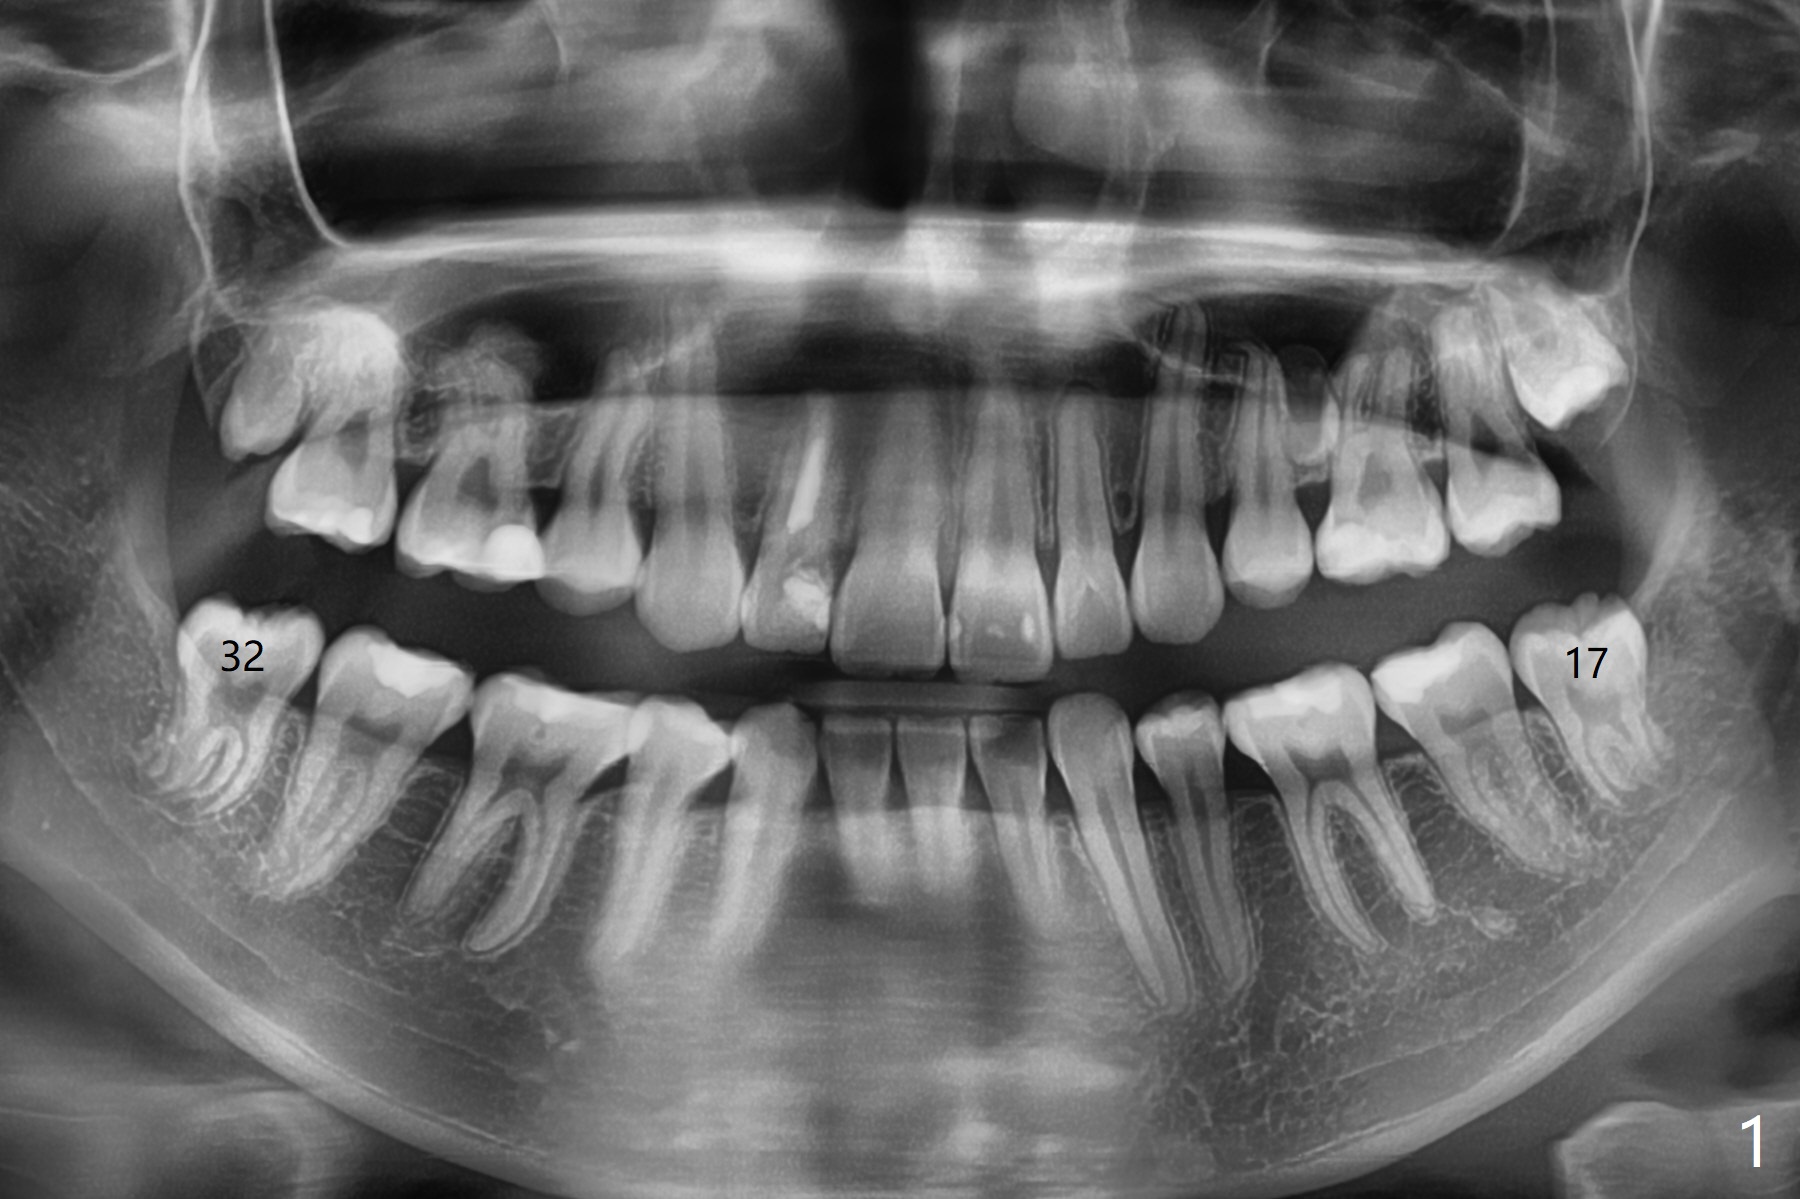

19岁女抱怨右下智齿远中龈下食物坎塞,不希望拔除,因为缺牙太多:先天性缺失一个下切牙,为了矫正又拔除4个双尖牙(图一)。临床检查32号牙远中牙龈覆盖(图二:*),而17号牙萌出不多(图三),没有食物坎塞史。局麻下,使用Diode Laser (Picasso)切除牙龈直到智齿远中咬合面暴露(图四)。术后突然意识到为了防止牙龈重新覆盖,必须做crown lengthening,也就是切除远中骨质(图五(黑色),与图一’对比),是吗?随访时利用Shining口扫记录,拍摄角度好。